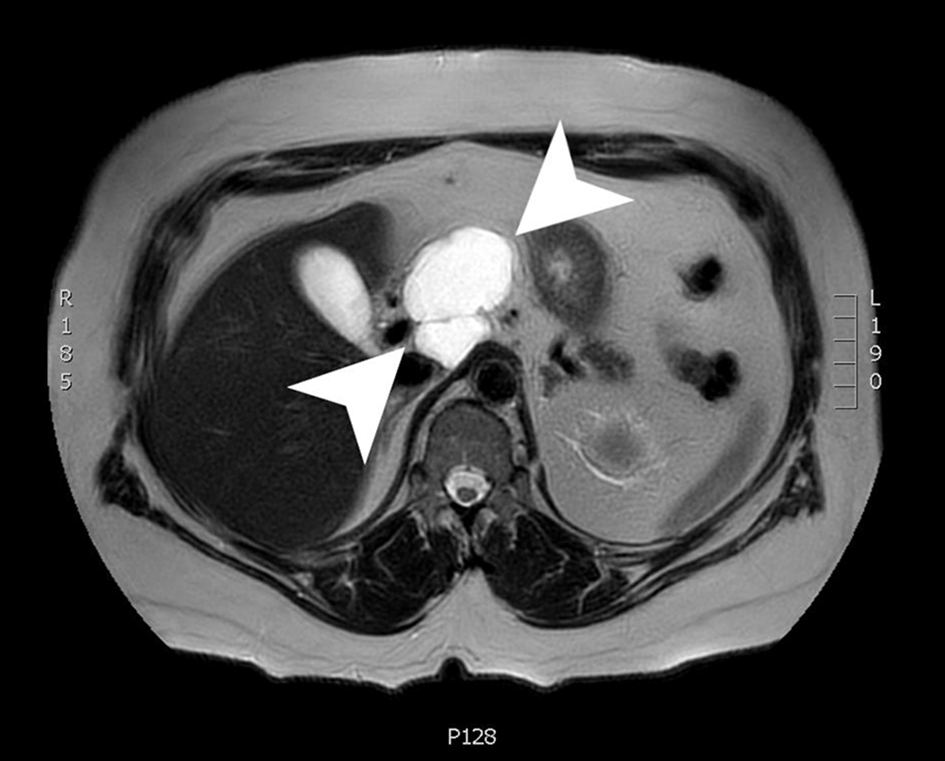

A magnetic resonance imaging (MRI) scan 3 months later showed an interval decrease in size to 6.1 × 4.3 × 5.3 cm. The cyst was a lobulated, macrocystic mass extending superiorly from the anterior pancreas body and draping over the portal vein and common hepatic artery while exerting a mass effect on the posterior wall of the gastric antrum. The cyst wall demonstrated irregular enhancement with regions of restricted diffusion (Fig. 3). The patient was advised to follow up in 3 months with a CT scan to continue to monitor the size of the lesion. Due to the imaging and EUS characteristics, this lesion is felt to be a lymphangioma and will be followed.

![]() Click for large image | Figure 3. An axial slice from a T2-weighted MRI with gadolinium contrast showing a 6.1 × 4.3 × 5.3 cm lobulated, cystic mass with a few internal septations. MRI: magnetic resonance imaging. |